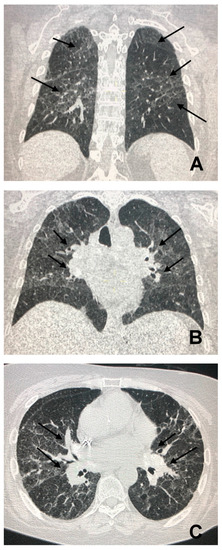

2. Sarcoidosis, the Chameleon Disease

3. CT in Pulmonary Sarcoidosis, Imaging Findings and Classification